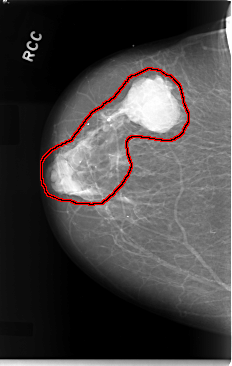

FILE: C_0019_1.RIGHT_CC.OVERLAY

TOTAL_ABNORMALITIES 1

ABNORMALITY 1

LESION_TYPE MASS SHAPE LOBULATED MARGINS CIRCUMSCRIBED

ASSESSMENT 5

SUBTLETY 5

PATHOLOGY MALIGNANT

TOTAL_OUTLINES 1

BOUNDARY